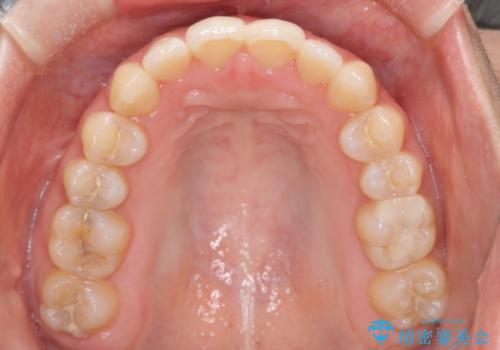

初診時の歯並びの状態としては、上下ともに全体に及ぶの中等度以上のがたつき(叢生)があり、前歯数本が反対交合の状態でした。

強い叢生がありましたが、抜歯は行わず上下顎ともに、主に歯列弓の拡大とディスキング(歯と歯の間に隙間を作る処置)を行い叢生を改善しました。